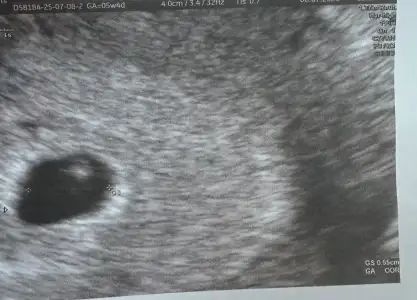

Selamlar teyzoşlar 6 haftalık ilk kontrole gittim hersey yolunda cok şükür kalp atışıda duyduk 6+1 cikti ultrason olcumune gore 🤲🏻 darısı sizlere olsun

• IMG_20250708_101635.webp

IMG_20250708_101635.webp

47,5 KB · Görüntüleme: 84